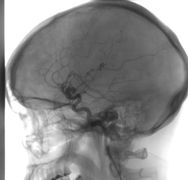

Zobacz moją historię do sierpnia 2024 r. i dramatyczną, wycieńczającą walkę po odkryciu tej rzadkiej choroby.

Tylko operacja w USA daje mi szanse na dalsze życie !!!